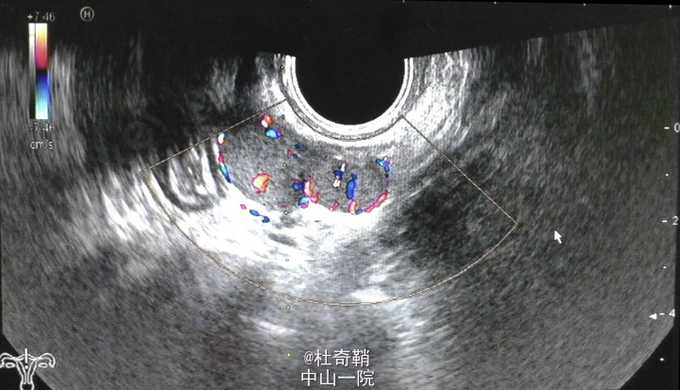

体检:腹部触诊无压痛及反跳痛,妇检无异常。 CA125:70.42 U/ml (正常值0–35 U/ml)。其他血清学检查无明显异常。 阴超提示直肠子宫陷凹可见高血流信号结节。 CT平扫+增强:直肠子宫陷凹处可见一不规则小结节及多发圆形小结节。大网膜处可见多发小结节,最大直径为1.4cm。盆腔内可见两个小包块,均在直肠子宫陷凹处,与其他结节呈现相似的密度和外形。 患者行B超引导下的后穹窿穿刺术取组织,细胞学及活检提示非恶性细胞及组织,考虑为脾组织植入。